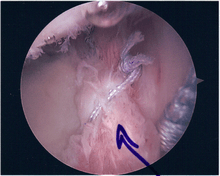

Surgical treatment of SLAP tears has become more common in recent years. The success rate for repairing isolated SLAP tears is reported between 74-94%.[8] While surgery can be performed as a traditional open procedure, an arthroscopic technique[9] is currently favored being less intrusive with low chance of iatrogenic infection.[10]

Procedure

Following inspection and determination of the extent of injury, the basic labrum repair is as follows.

- The glenoid and labrum are roughened to increase contact surface area and promote re-growth.

- Locations for the bone anchors are selected based on number and severity of tear. A severe tear involving both SLAP and Bankart lesions may require seven anchors. Simple tears may only require one.

- The glenoid is drilled for the anchor implantation.

- Anchors are inserted in the glenoid.

- The suture component of the implant is tied through the labrum and knotted such that the labrum is in tight contact with the glenoid surface.